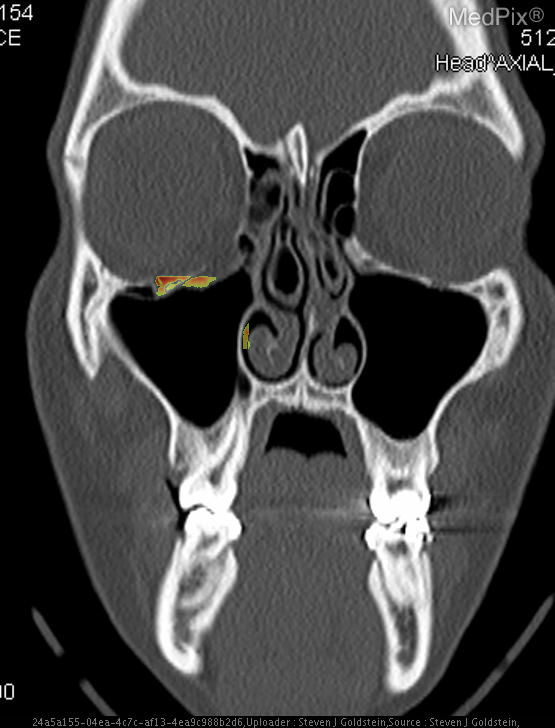

- Coronal CT image shows discontinuity of the orbital floor on the image-left (patient-right) side.

- Herniation of orbital fat and partial inferior displacement of soft tissue into the maxillary sinus on the image-left (patient-right).

- Air-fluid level within the right maxillary sinus (image-left side), consistent with hemorrhage or fluid collection.

- Intact orbital floor on the image-right (patient-left) side.

- Globes are intact bilaterally, without evidence of rupture or significant intraorbital hematoma.

- Nasal septum roughly midline; ethmoid air cells and remaining paranasal sinuses are clear.

- No intracranial abnormalities visible at this coronal slice level.

Orbital floor (blowout) fracture on the image-left (patient-right) side. The CT demonstrates a defect in the orbital floor with herniation of orbital contents into the maxillary sinus, a classic feature of a blowout fracture. The presence of sinus fluid and continuity of orbital fat confirms disruption of the orbital floor. Context consistency: Consistent. Context title and imaging findings are in agreement for an orbital floor fracture. Confidence: 95%.